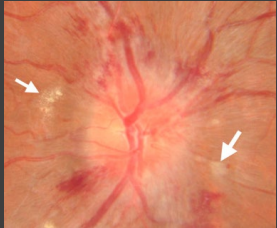

retina, increased, disc, color, hypertension, meningitis

Fundoscopic Exam

-Visual inspection of _______, vessels, and optic disc

-Papilledema/optic disc edema indicates ___________ ICP

-Look for sharp optic _____ margins, smoothness of vessels, observe the ______ of the disc and look for hemorrhages and exudate

-Differential diagnosis → idiopathic intracranial ___________, venous thrombosis, intracranial mass lesion, hydrocephalus, __________, and optic neuritis